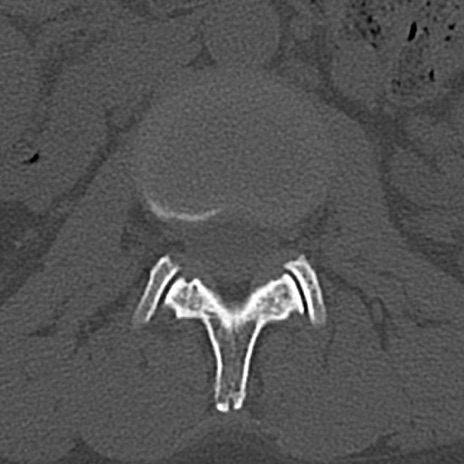

【整形】TIPS症例4 腰椎CT(横断像)

腰椎CT

横断像と矢状断像